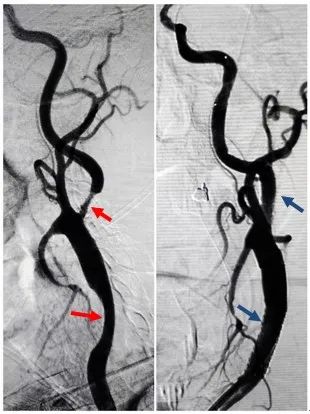

术前造影显示:

左侧颈动脉串联性重度狭窄(红箭头);

术后狭窄完全解除(蓝箭头)